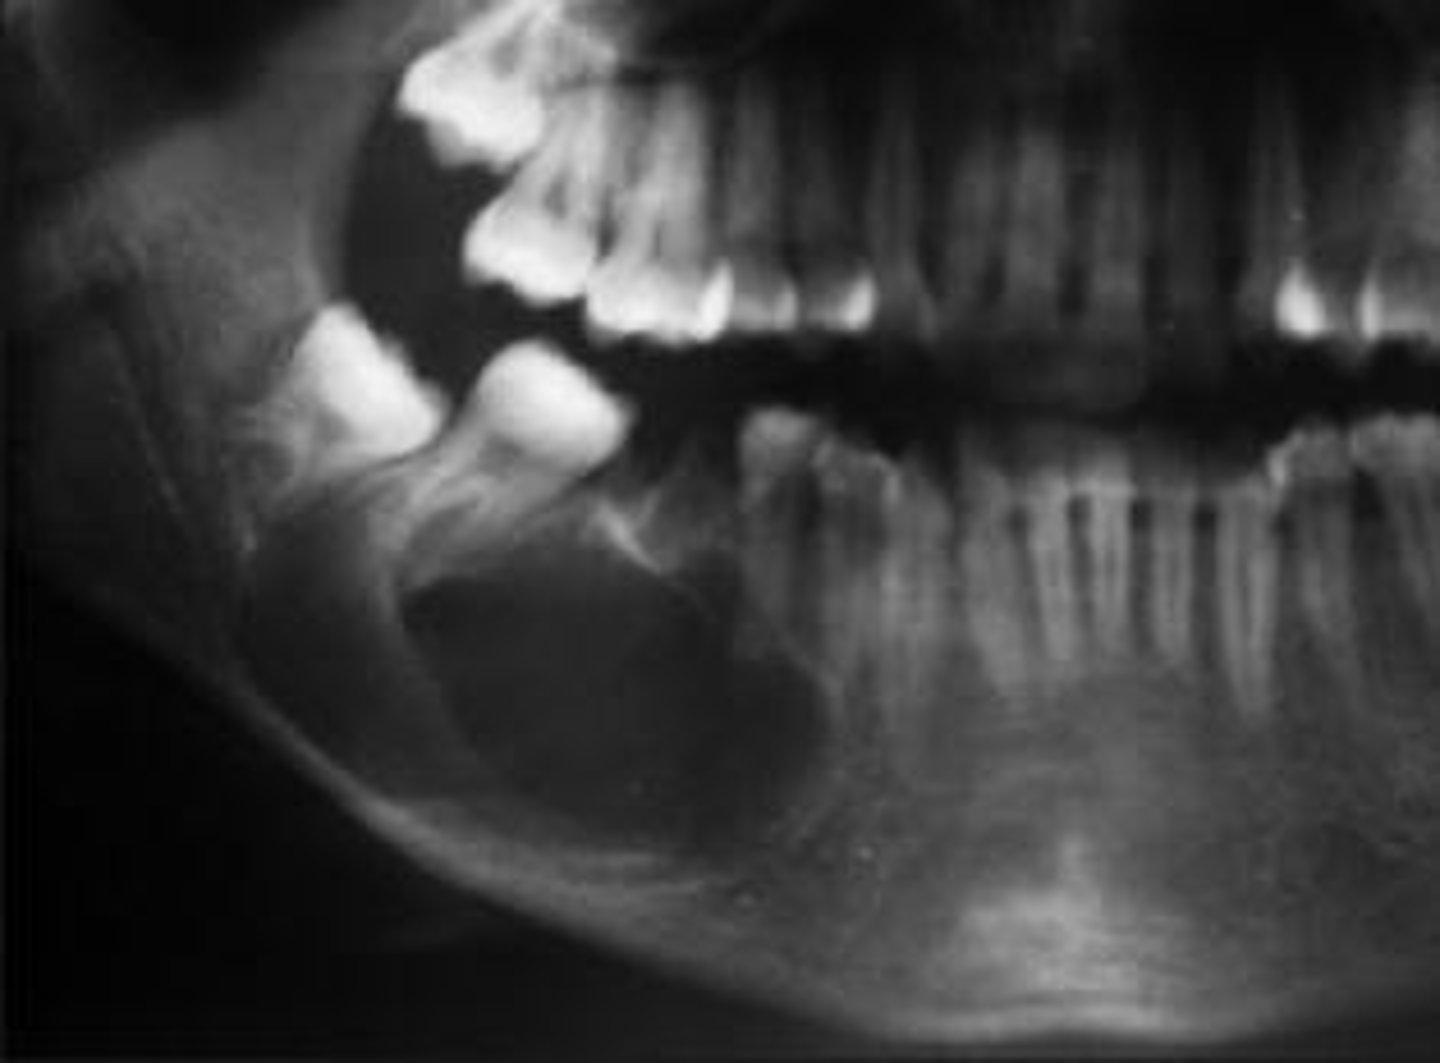

What are the radiographic features of ameloblastomas?

⢠unilocular radiolucency (early lesions)

⢠multilocular radiolucency (honeycomb/soap bubble) (large lesions)

⢠cortical thinning/bone expansion

⢠resorption of adjacent tooth roots + tooth displacement